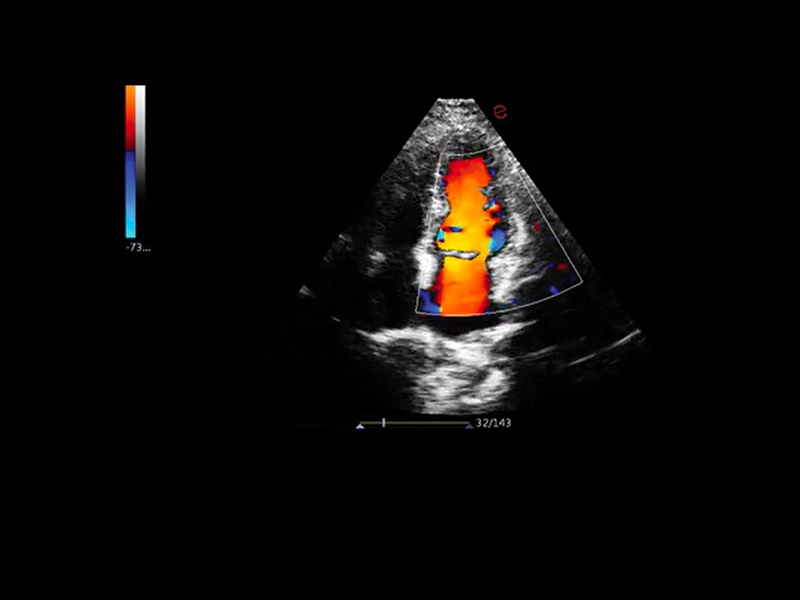

Q7 - Cardio CFM

Q7 - Cardio CFM

MyLab™X1 - Apical view CFM

MyLab™X1 - Apical view CFM